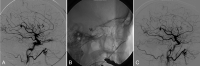

Fig. 1.

A, Pre-embolization right CCA. Frontal projection arterial phase shows the dural CCF with early venous drainage into the left cavernous sinus followed by the left IPS. B, Lateral projection of right CCA injection late capillary phase shows retrograde filling of abnormally dilated left SOV. C, Unsubtracted lateral projection image demonstrates transjugular-IPS venous access to the left SOV and deployed coils in the left SOV. D, Lateral view of the right CCA injection shows the repositioned microcatheter to the anterior compartment of the cavernous sinus and partial embolization with Onyx. E and F, Postembolization CCA angiogram. Frontal projection (E) and lateral projection (F) demonstrate complete obliteration of the fistula. Deployed coils in the left SOV and Onyx cast in the left cavernous and coronary sinuses block the fistula. There is no residual fistula.